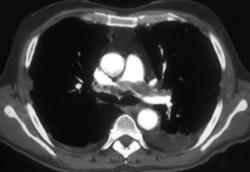

Nice Azygos Vein in 3D